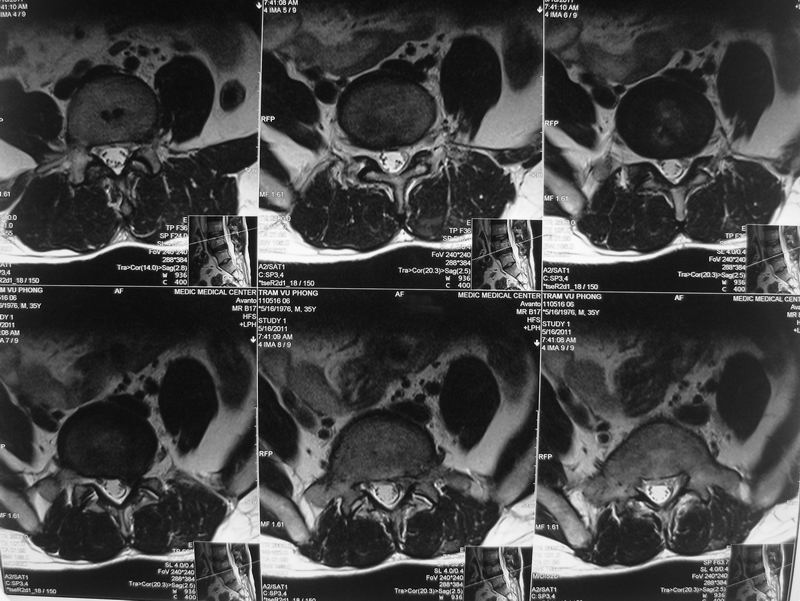

16-5-2011 L4-5DH

• 16-5-2011 L4-5DH